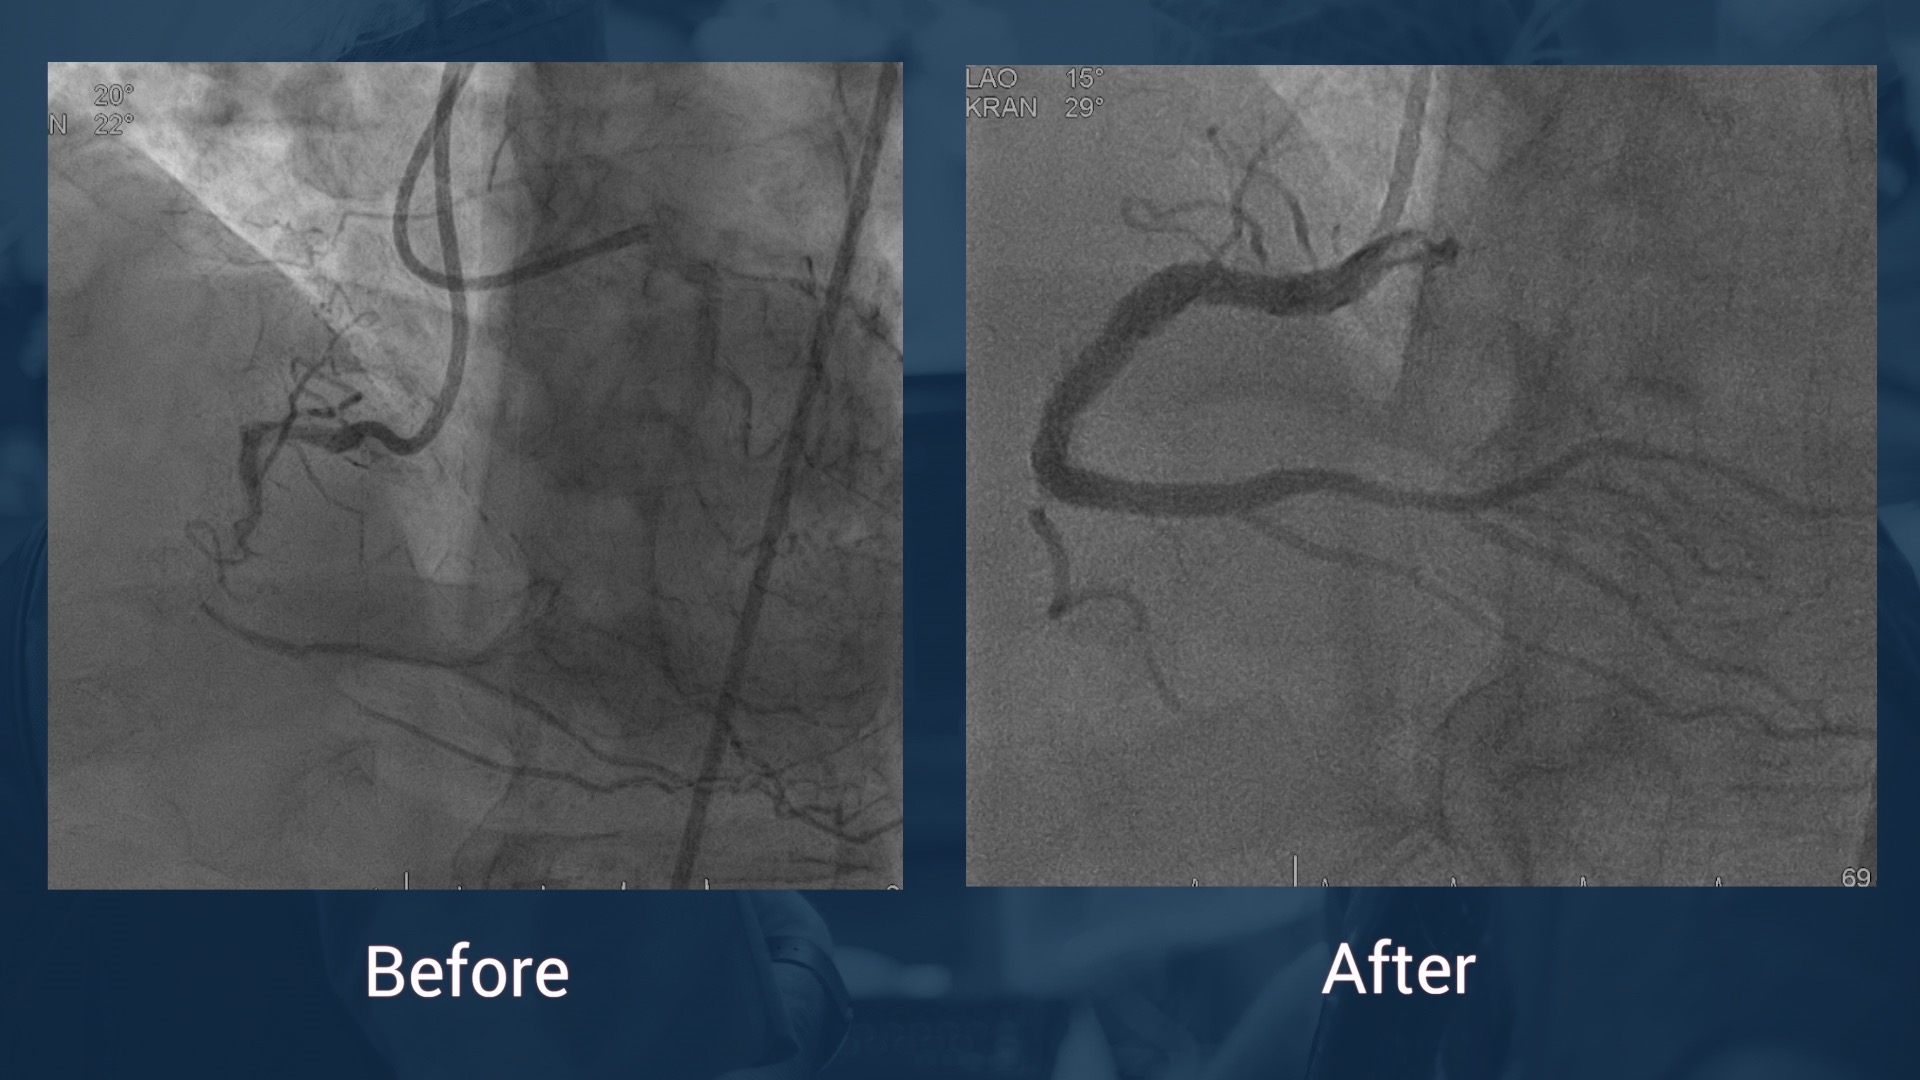

CAG 14.7.17: LAD without stenosis, CX without stenosis, in-stent reocclusion of the RCA